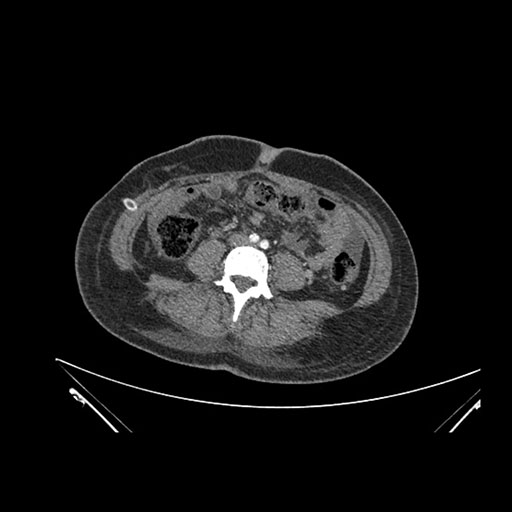

Imaging Analysis

Look through the patient's CT scan to identify any areas of concern for the necessary procedure.

Coronal Arterial

Based on initial findings, which issue(s) would you be most concerned about?